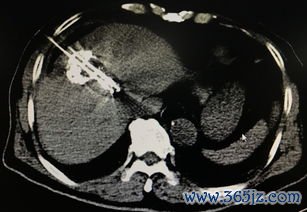

微波消融:微波加热烧死肿瘤

精准微创的肿瘤“高温手”——微波消融技术原理与应用 在肿瘤治疗领域,一场“静悄悄的革命”正在发生。它无需传统外科手术的大切口,也避免了放化疗带来的全身性副作用,仅凭一根细如笔芯的微波针,就能在影像设备的精准引导下,深入病灶核心,利用高温对肿瘤实施“定点清除”。这项技术便是微波消融术(Microwave Ablation, MWA),一种以微创和精准为核心优势...